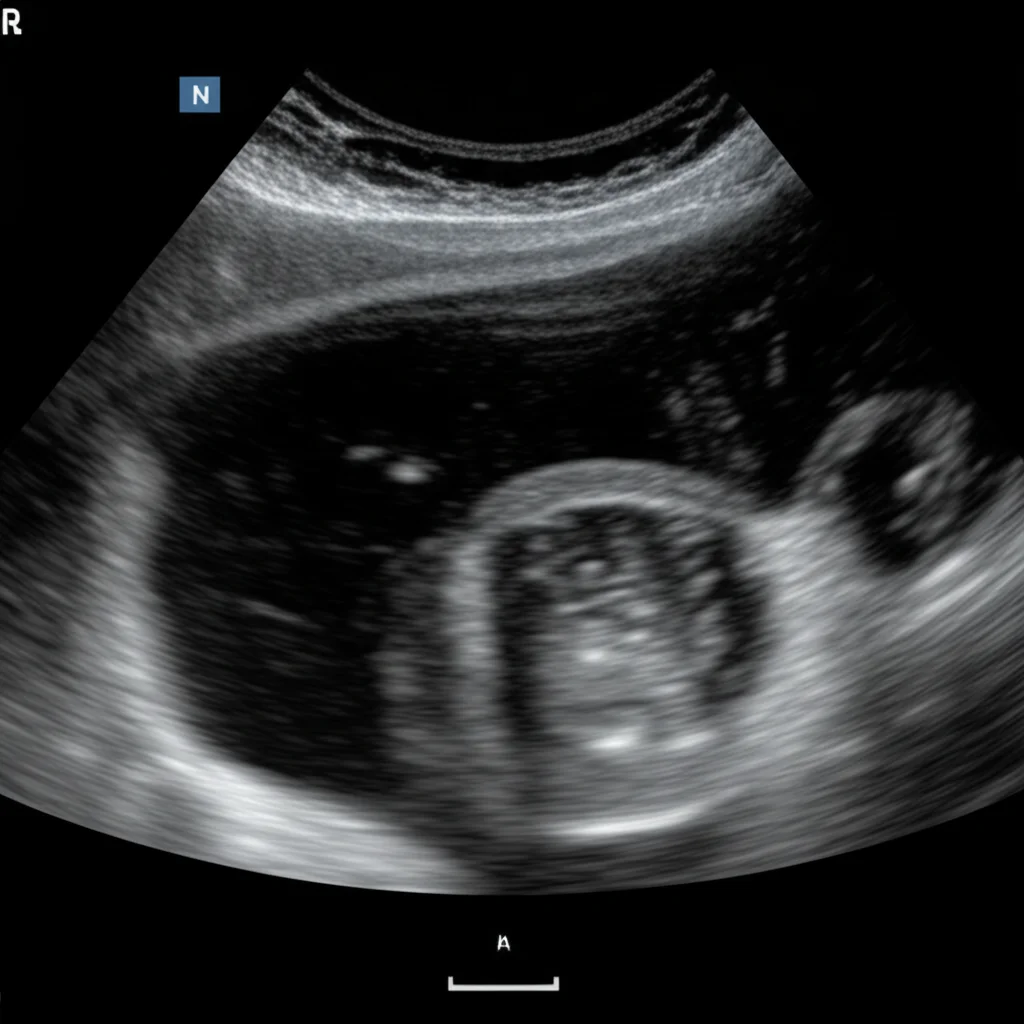

That’s where the **Tiger Model** comes in. Think of it as a special kind of AI that can create images based on text descriptions. We fused clinical insights – all those specific details about how a rare thyroid nodule might appear (its shape, texture, edges, location, etc.) – with powerful image generation technology, specifically diffusion models.

The goal? To produce synthetic ultrasound images that are so realistic and diverse, they can effectively teach AI models to spot these rare subtypes, even when real-world data is limited.

A clever part of the Tiger Model is how it handles the image. It uses separate components (encoders) to focus on the nodule itself (the “foreground”) and the surrounding thyroid tissue and neck structures (the “background”). This allows for really fine-grained control over the generated image details, making them much more convincing and clinically accurate. We used things like segmentation masks to tell the model exactly where the nodule is and edge detection (like a digital sketch) for the background structure.